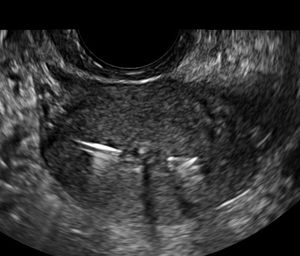

Pelvic sonography, especially transvaginal 3D imaging, is critical for identifying malpositioned and embedded IUDs.